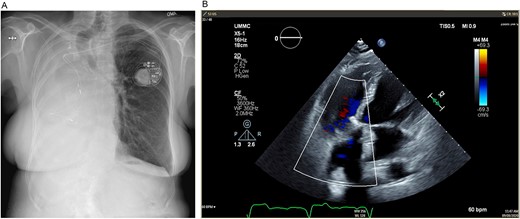

Turning attention to the tricuspid valve, pledgeted, transannular 2–0 Ethibond sutures were placed circumferentially in everting fashion (atrial side to ventricular side), taking care to place superficial sutures buttressed with the septal leaflet near the atrioventricular node. The annular sutures were brought through the sewing ring of a 33 mm St. Jude Medical Epic bioprosthetic valve that was seated on the annulus, and the annular sutures were secured and cut using the CoreKnot device (LSI Solutions; Minneapolis, MN). Leaflet motion and competence of the valve were confirmed with saline. The right atriotomy was then closed in two layers of 4–0 Prolene. After delivering a dose of terminal warm blood cardioplegia, the aortic cross-clamp was released on low flow CPB. The heart was reperfused, and normal sinus rhythm resumed. With normal biventricular function, the patient was weaned and decannulated of CPB. After achieving hemostasis, the right posterolateral thoracotomy incision was closed. The patient was then taken to the cardiovascular intensive care unit in stable condition. On 8-month follow-up, mean gradient across the tricuspid valve prosthesis was 5 mmHg, RV size and function had returned to normal and the patient had normal exercise tolerance and was feeling well (Fig. 3).

(A) Postoperative posteroanterior view chest X-ray. (B) Postoperative transesophageal echocardiogram with doppler showing a well-seated bioprosthetic valve in the tricuspid position with a mean gradient of 4 mmHg and no measurable insufficiency.